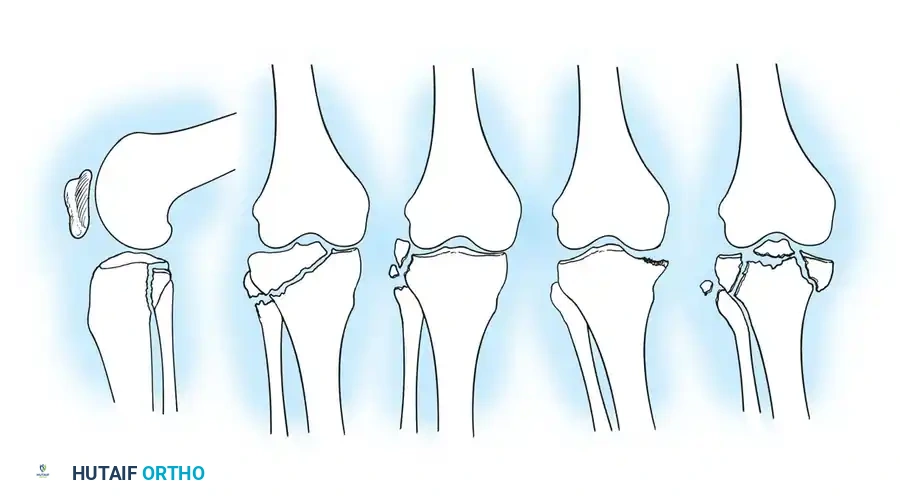

أنماط الكسور المصحوبة بخلع

تحمل هذه الأنماط خطورة أعلى بكثير وتترافق مع تمزقات الغضاريف والأربطة.

أنواع كسور وخلع هضبة التيبيا

تفاصيل إضافية لكسور هضبة الساق

تأثير الكسور على أربطة الركبة

تشمل هذه الأنماط الانقسامات التاجية، وكسور اللقمة الكاملة، وانفصال الحواف، والكسور الرباعية الأجزاء المدمرة التي تفقد الركبة استقرارها بالكامل.